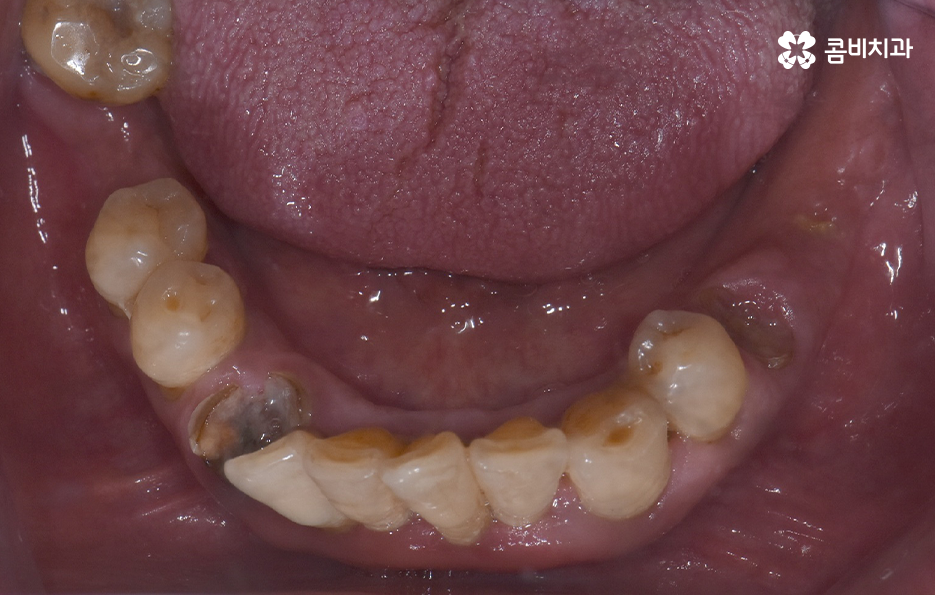

치주염으로 인해 잇몸이 내려앉고 치아의 뿌리가 흔들려서 발치했어요

위 환자분의 엑스레이 사진을 보면 치아의 뿌리 부분에 가깝게 잇몸이 내려앉은 것을 볼 수 있는데 치아의 구조에서 뿌리쪽은 법랑질이 없기 때문에 잇몸이 내려앉고 잇몸 뼈가 치주염으로 녹게 되면 치아가 너무 아파서 식사를 하기에도 어렵고 물 한잔만 마셔도 이가 시릴 정도로 일상에 지장을 느끼실 수 있어요